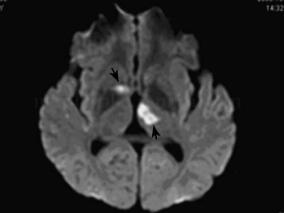

1小时条评论25岁男性,突发右眼视物不清5天,右下肢活动不利伴精神障碍2天。入院前15天曾在突然出现右眼视物不清,随后出现昏睡,叫醒困难。在北京同仁医院眼科诊断为右眼底出血并给予治疗后症状减轻。随后头颅MR检查提示多发性脑梗死。奇怪的是该青年的症状与常见的青年型脑卒...